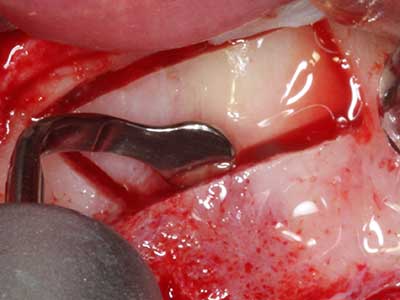

En la extracción de bloques óseos la piezocirugía también presenta ventajas adicionales: Además de la alta precisión en la osteotomía que ya se ha descrito antes, se ha comprobado que el uso de los delgados insertos de sierra resulta especialmente cuidadosas con el hueso. Frente a esto, sobre todo cuando se usan las fresas de Lindemann, cabe esperar pérdidas en la extracción significativamente más altas debido al mayor grosor de la parte frontal del cabezal (Lakshmiganthan, Gokulanathan et al. 2012). La separación basal que se necesita en particular en los injertos de bloque extraídos de forma retromolar se ve facilitada mediante sierras perpendiculares especialmente previstas a tal fin, lo que permite considerar que la cirugía piezoeléctrica es un procedimiento preciso y seguro para la obtención de bloques de hueso en el área retromolar (Happe 2007) (fig. 1-12).

Aplicación: Partición ósea / Cortical Split